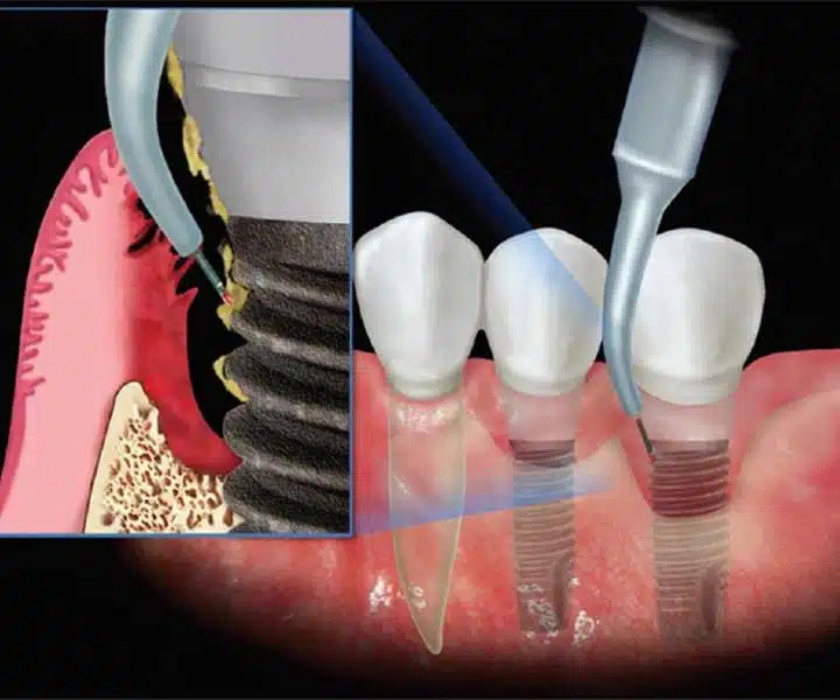

Cấy ghép Implant nha khoa được xem là giải pháp phục hồi răng mất tối ưu nhất hiện nay, có khả năng tồn tại hàng chục năm, thậm chí trọn đời nếu được thực hiện đúng kỹ thuật và chăm sóc đúng cách. Tuy nhiên, thực tế cho thấy không ít trường hợp Implant chỉ dùng được vài năm đã gặp vấn đề như lỏng trụ, viêm quanh Implant, tiêu xương… Nguyên nhân không phải luôn nằm ở chất lượng trụ hay tay nghề bác sĩ, mà nhiều khi bắt nguồn từ những sai lầm tưởng chừng vô hại của người bệnh.

Sai lầm 2: Lựa chọn cơ sở không đảm bảo tay nghề và trang thiết bị

Công nghệ Implant hiện đại đòi hỏi sự kết hợp giữa tay nghề bác sĩ, hệ thống máy móc chẩn đoán – hỗ trợ phẫu thuật và quy trình vô trùng nghiêm ngặt.

Không ít bệnh nhân chọn nơi thực hiện chỉ dựa vào giá rẻ mà bỏ qua yếu tố chuyên môn. Thực tế, cấy ghép Implant không chỉ đơn giản là “đặt trụ vào xương” mà cần tính toán chính xác vị trí, góc độ, lực tác động… để trụ ổn định và chịu lực tốt lâu dài.

Nguyên nhân: Tay nghề hạn chế, thiếu thiết bị hỗ trợ (như máy CT Cone Beam 3D, phần mềm lên kế hoạch điều trị cụ thể, công nghệ phẫu thuật hướng dẫn) làm tăng nguy cơ đặt trụ sai vị trí hoặc không đủ độ vững.

Hệ quả: Trụ Implant bị quá tải khi ăn nhai, dẫn đến tiêu xương, viêm quanh trụ, thậm chí gãy trụ.

Sai lầm 3: Không tuân thủ hướng dẫn chăm sóc sau cấy ghép

Giai đoạn 3–6 tháng sau khi đặt trụ là thời điểm xương hàm tích hợp với Implant. Nếu bệnh nhân không tuân thủ hướng dẫn chăm sóc, nguy cơ thất bại sẽ tăng cao.

Sai lầm 4: Không tái khám định kỳ

Implant cần được theo dõi định kỳ để kịp thời phát hiện các vấn đề như viêm nướu, viêm quanh Implant, tiêu xương sớm hoặc hỏng mão sứ.